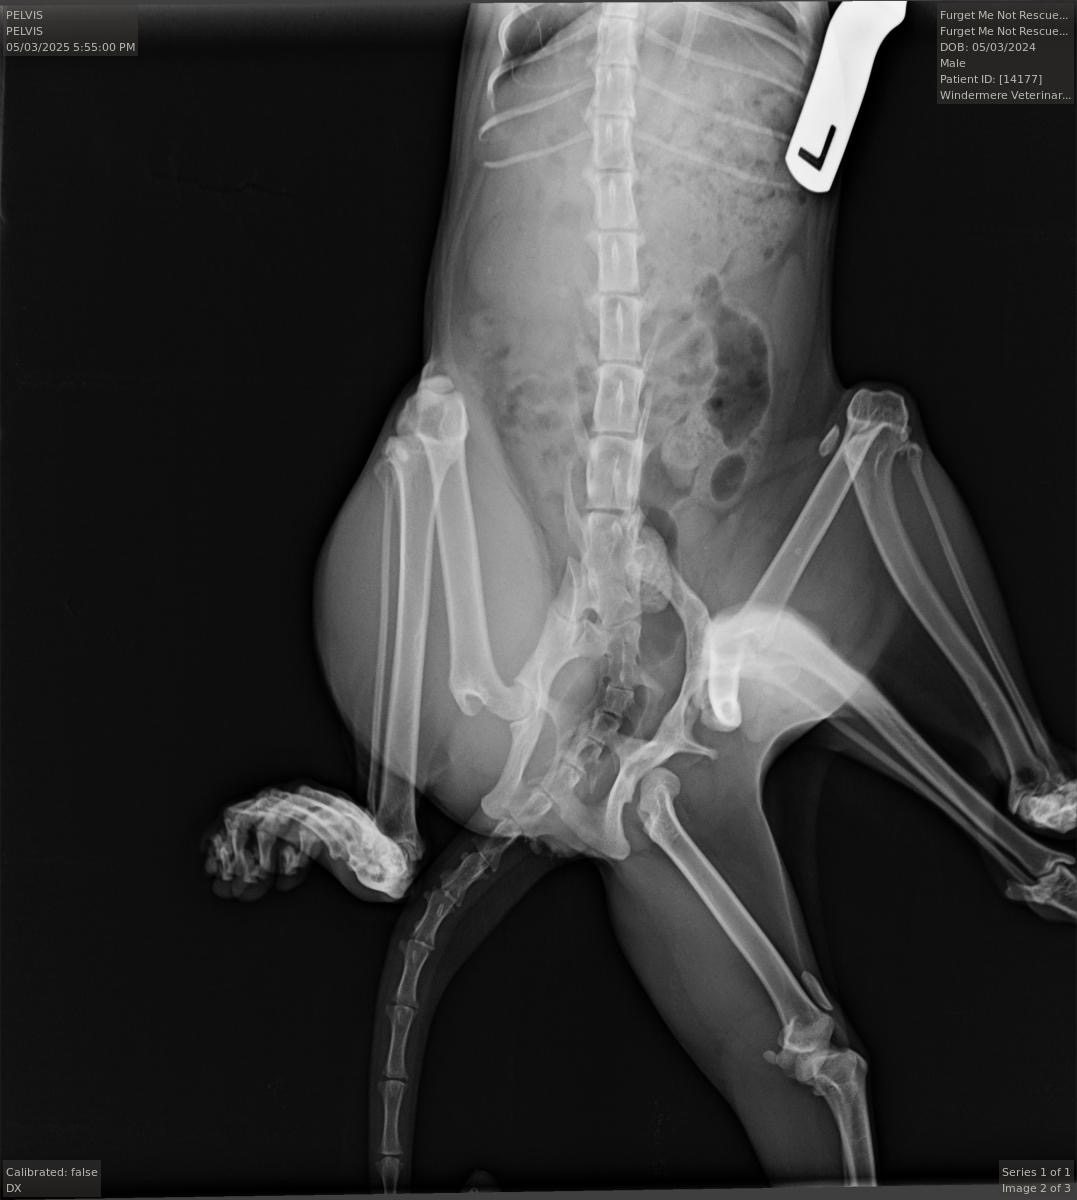

Not only is Bitsy a sweet and beautiful kitty, but she’s one in 1 million. Bitsy has six legs! This condition was most likely caused by absorbing part of her twin in utero. She was born with an extra pelvis and 2 extra legs.

Unfortunately, in addition to her extra legs being atrophied and nonfunctional, her hind leg is also attached to the second pelvis that’s nonfunctioning, and rotated completely backwards, causing her to drag it painfully behind her, covered in sores.